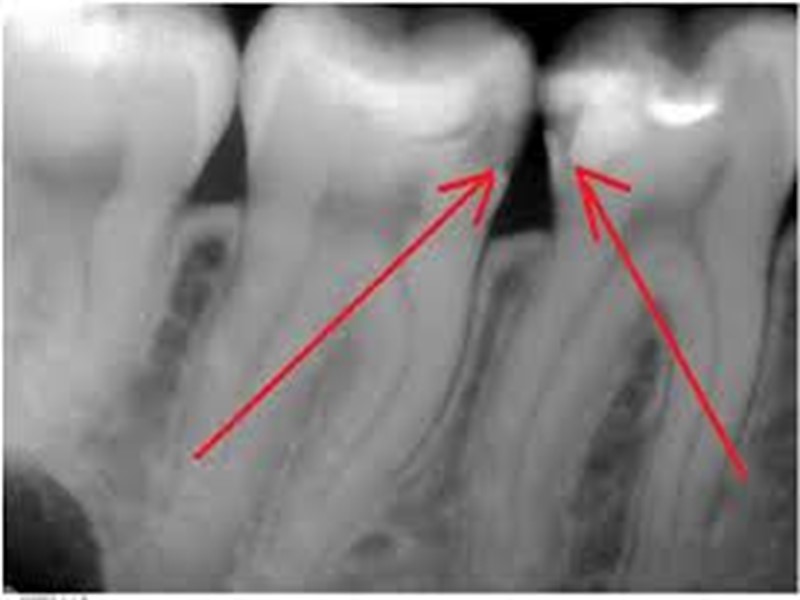

Классификация по локализации: Фиссурный кариес. Контактный (апроксимальный) кариес. Пришеечный (цервикальный) кариес. Циркулярный (кольцевой) кариес.

Второй класс

Дифференциальная диагностика поверхностного, среднего и глубокого кариеса Общее: 1. жалобы на боли от раздражителей, быстропроходящие после их устранения; 2. причина возникновения - зубная бляшка, локальное снижение рН; 3. возникает после прорезывания, содержание фтора в питьевой воде меньше 0,8-1 мг/л; 4. поражаются молочные и постоянные зубы; 5. прогрессирует, осложняется пульпитом и периодонтитом; 6. локализация, характерная для кариеса; 7. кариозная полость не сообщается с полостью зуба; 8. перкуссия безболезненна; 9. термодиагностика: возникает быстропроходящая боль на температурный раздражитель; 10. на рентгенограмме: кариозная полость не сообщается с полостью зуба, в периапикальных тканях изменений нет.